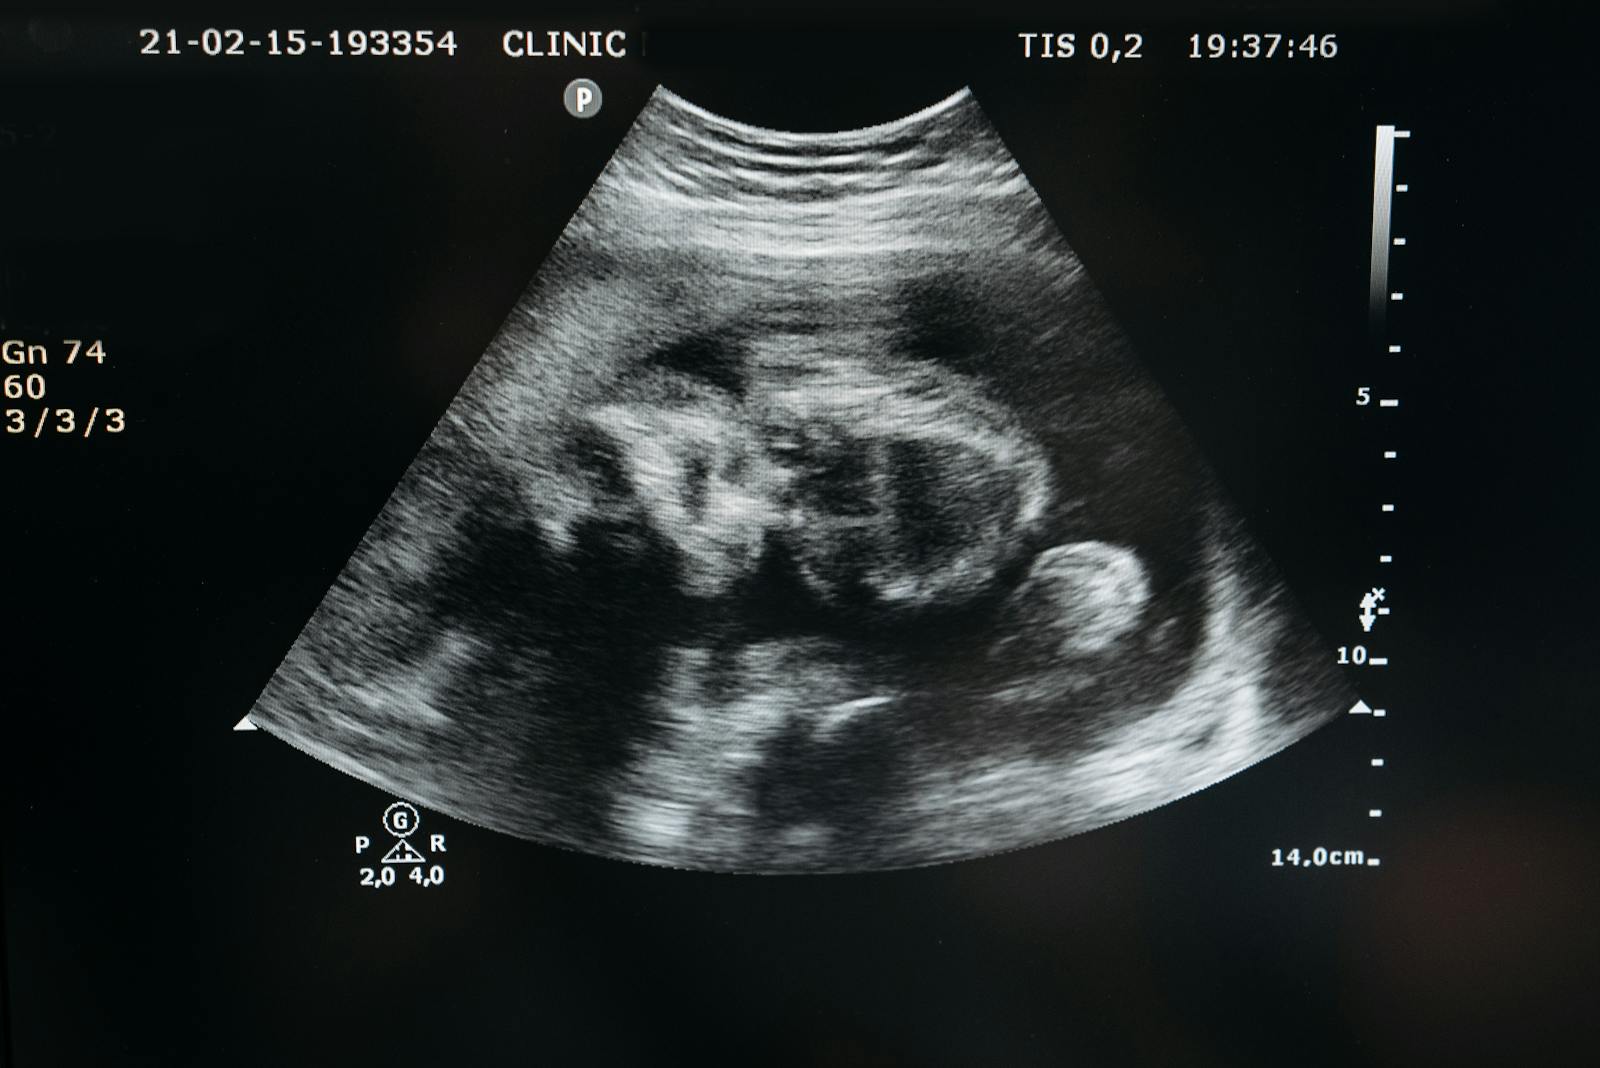

Understanding the Detailed Anomaly Scan at 20 Weeks

What the anomaly scan checks for and why it matters for your baby's development.